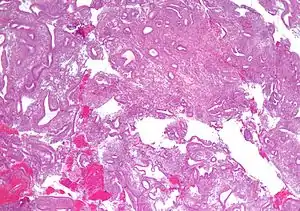

| Micrograph showing simple endometrial hyperplasia, where the gland-to-stroma ratio is preserved but the glands have an irregular shape and/or are dilated. Endometrial biopsy. H&E stain. | |

Endometrial hyperplasia is a condition of excessive proliferation of the cells of the endometrium, or inner lining of the uterus.

Like other hyperplastic disorders, endometrial hyperplasia initially represents a physiological response of endometrial tissue to the growth-promoting actions of estrogen. However, the gland-forming cells of a hyperplastic endometrium may also undergo changes over time which predispose them to cancerous transformation. Several histopathology subtypes of endometrial hyperplasia are recognisable to the pathologist, with different therapeutic and prognostic implications.[3]

- Endometrial hyperplasia (simple or complex) - Irregularity and cystic expansion of glands (simple) or crowding and budding of glands (complex) without worrisome changes in the appearance of individual gland cells. In one study, 1.6% of patients diagnosed with these abnormalities eventually developed endometrial cancer.[6]

- Atypical endometrial hyperplasia (simple or complex) - Simple or complex architectural changes, with worrisome (atypical) changes in gland cells, including cell stratification, tufting, loss of nuclear polarity, enlarged nuclei, and an increase in mitotic activity. These changes are similar to those seen in true cancer cells, but atypical hyperplasia does not show invasion into the connective tissues, the defining characteristic of cancer. The previously mentioned study found that 22% of patients with atypical hyperplasia eventually developed cancer.[6]